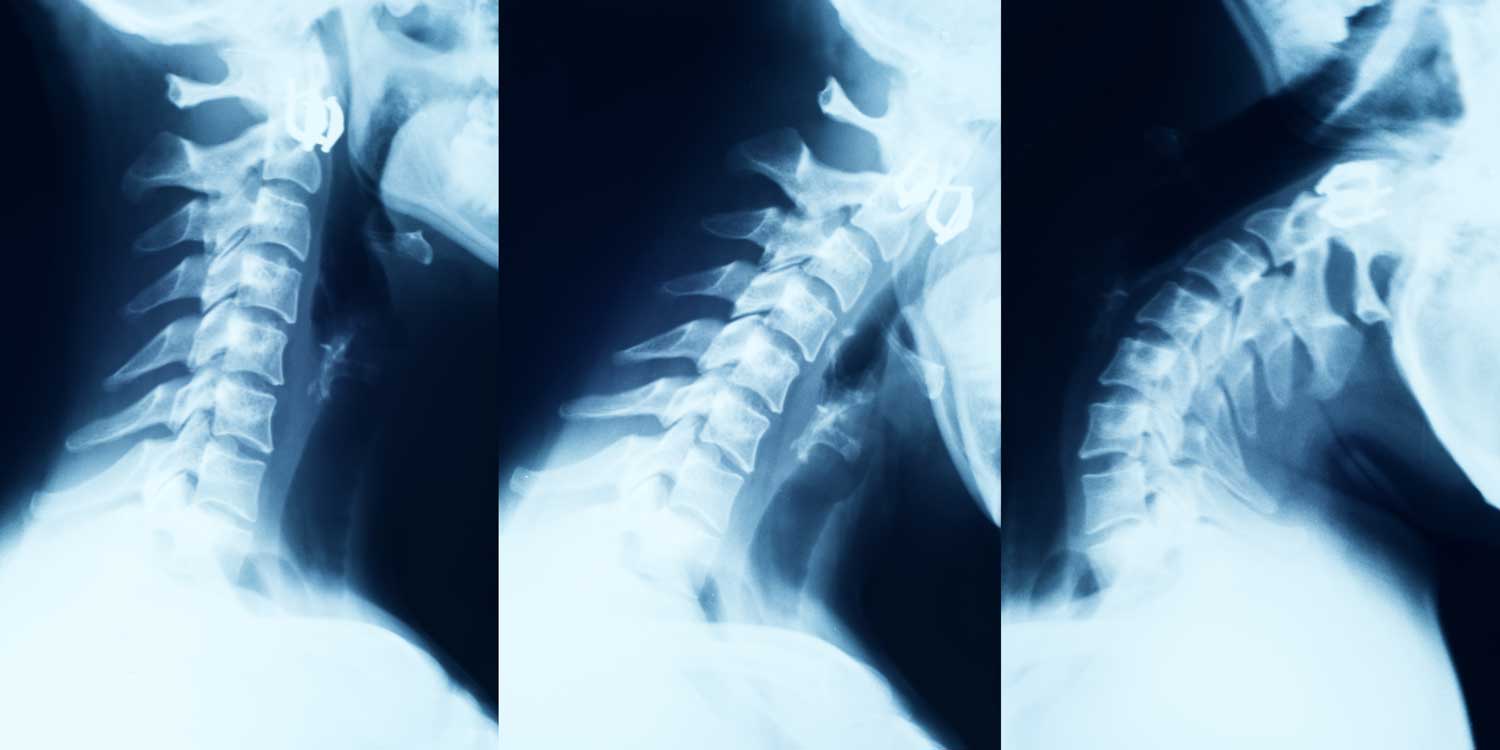

A neck X-ray — formally called a cervical spine X-ray or cervical spine radiograph — is the standard first-line imaging test for neck pain, injury, and stiffness. It produces detailed images of the seven cervical vertebrae (C1–C7), the disc spaces between them, the facet joints, and the overall alignment of the neck — giving your doctor essential information about fractures, arthritis, degenerative disc disease, and alignment abnormalities in a fast, painless exam.

The cervical spine is a complex structure: seven vertebrae, intervertebral discs, facet joints, and a network of ligaments — all compressed into a small space through which the spinal cord and the nerve roots to the arms pass. A cervical spine X-ray evaluates the bony architecture of this structure and provides important indirect clues about soft tissue conditions.

The lateral view is the most informative cervical spine X-ray projection, showing vertebral body alignment, disc space heights, the normal lordotic curve, and the prevertebral soft tissue — all critical for detecting fractures, degenerative disease, and instability.

The lateral view is the most informative single view of the cervical spine. Taken with the X-ray beam passing from one side of the neck to the other, it shows the vertebral bodies and disc spaces in profile, the overall curvature (lordosis), the four alignment lines that run along the anterior vertebral bodies, posterior vertebral bodies, spinolaminar line, and spinous process tips, and the prevertebral soft tissue. For the lateral view to be fully adequate, all seven cervical vertebrae must be visible down to the C7–T1 junction — if the shoulders obscure the lower vertebrae, a “swimmer’s view” with one arm raised is added.